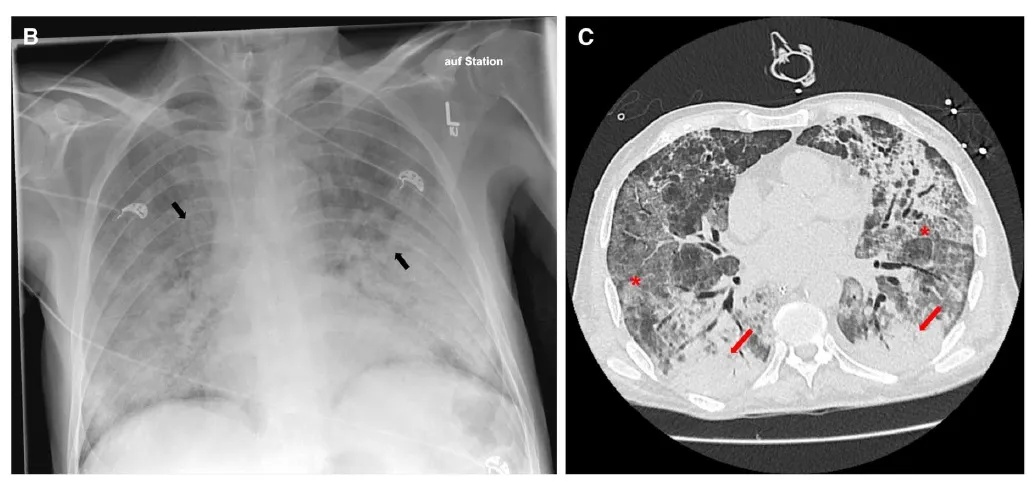

Sessão de desafio diagnóstico do NEJM que nos adiciona muito conhecimento sobre o tema vasculite!

Valkercyo Feitosa